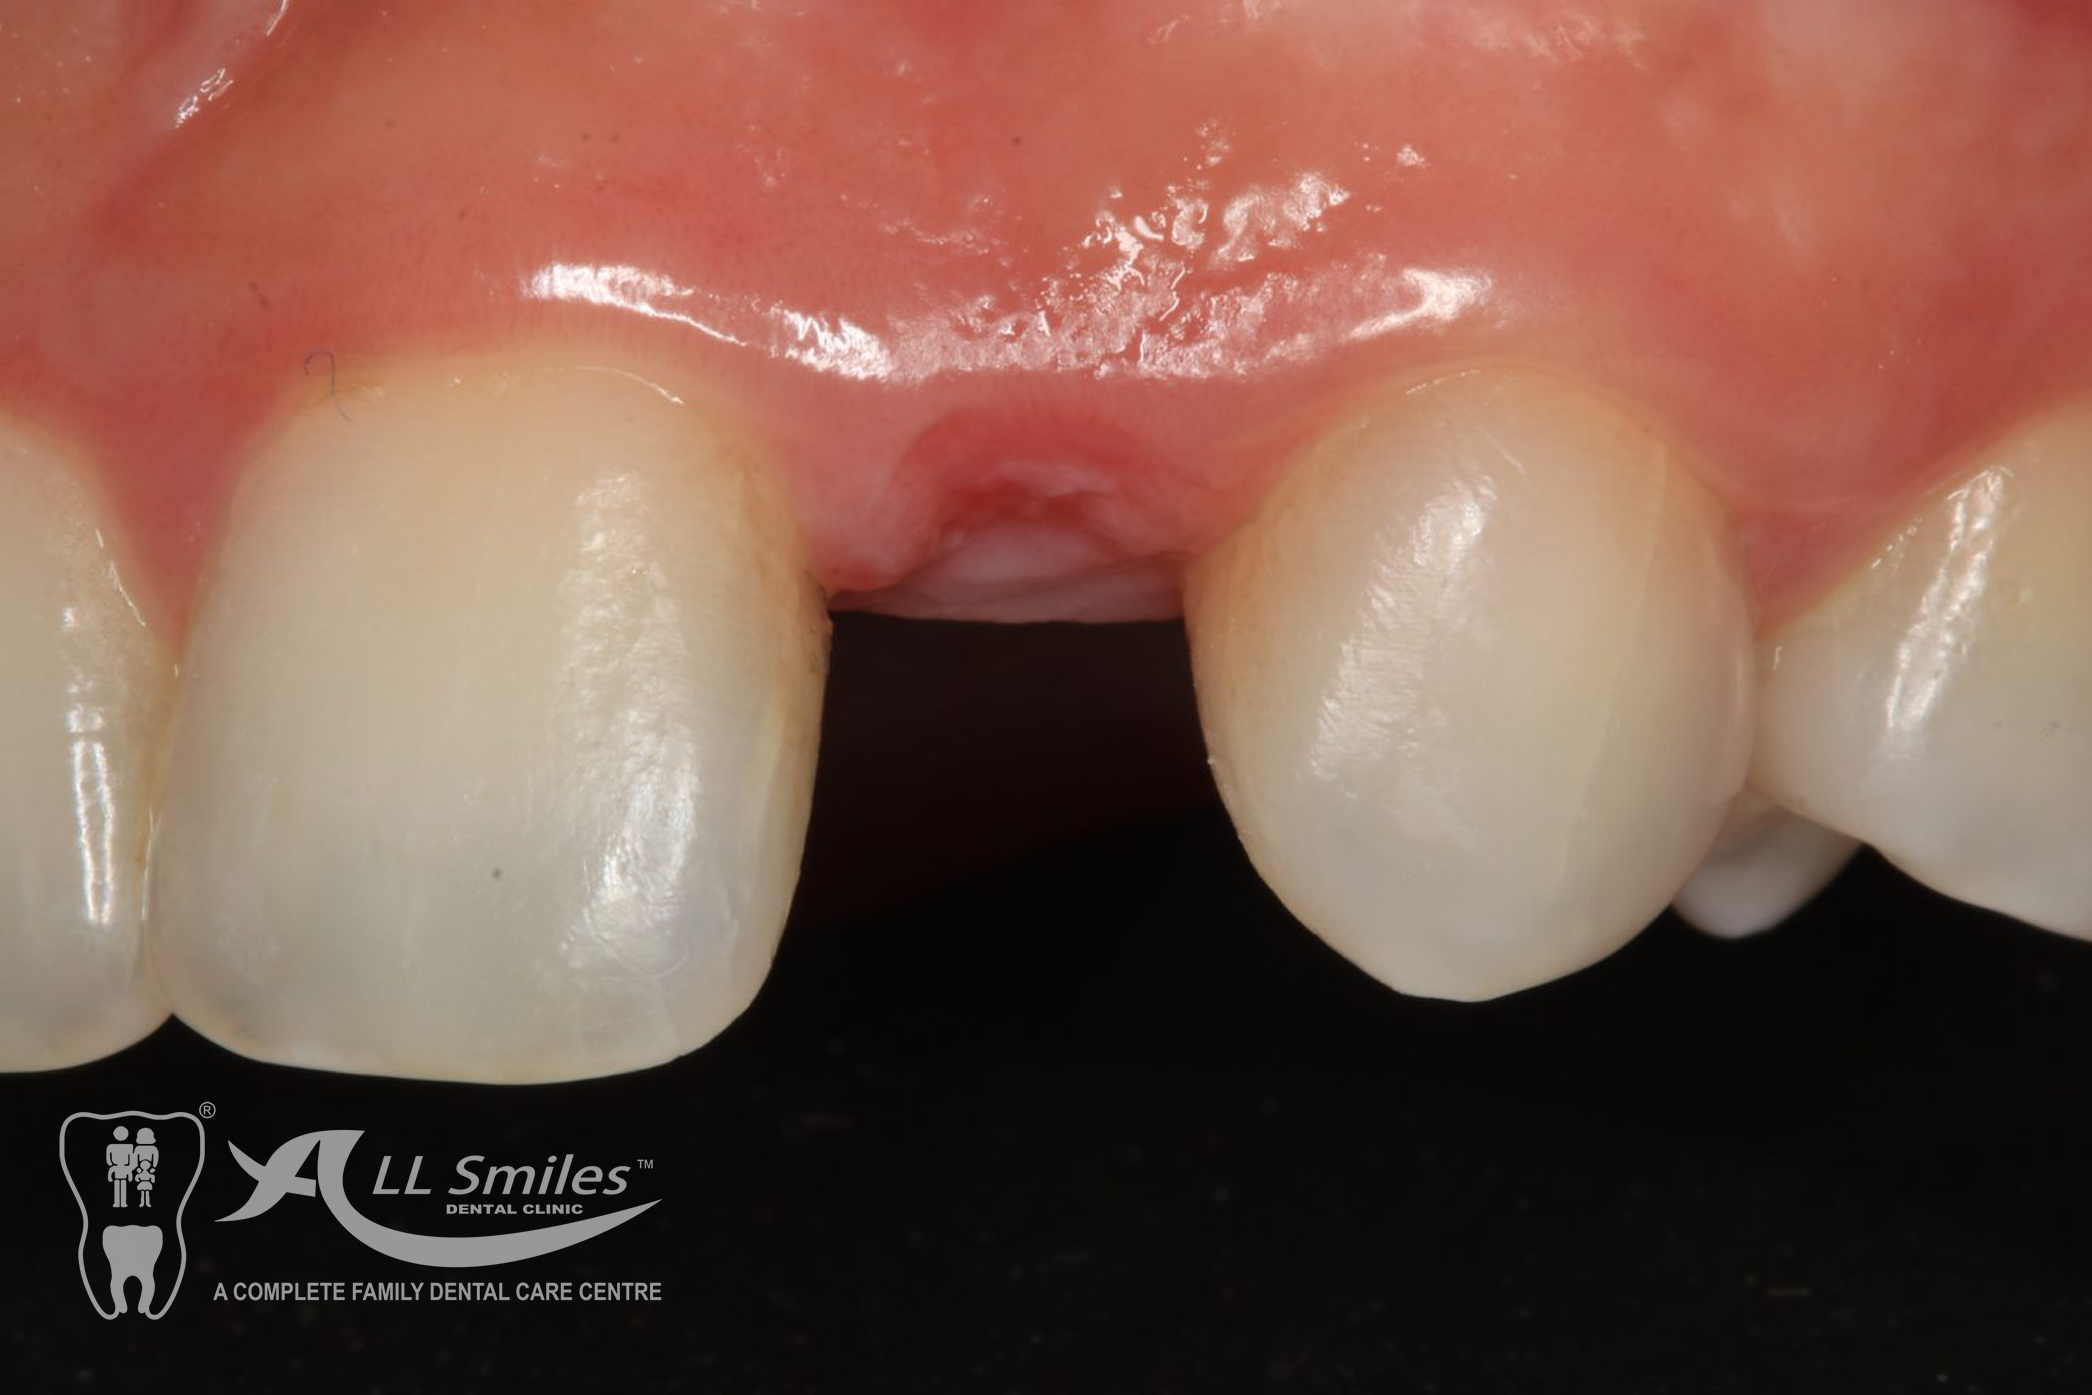

Crowns & Bridges Gallery